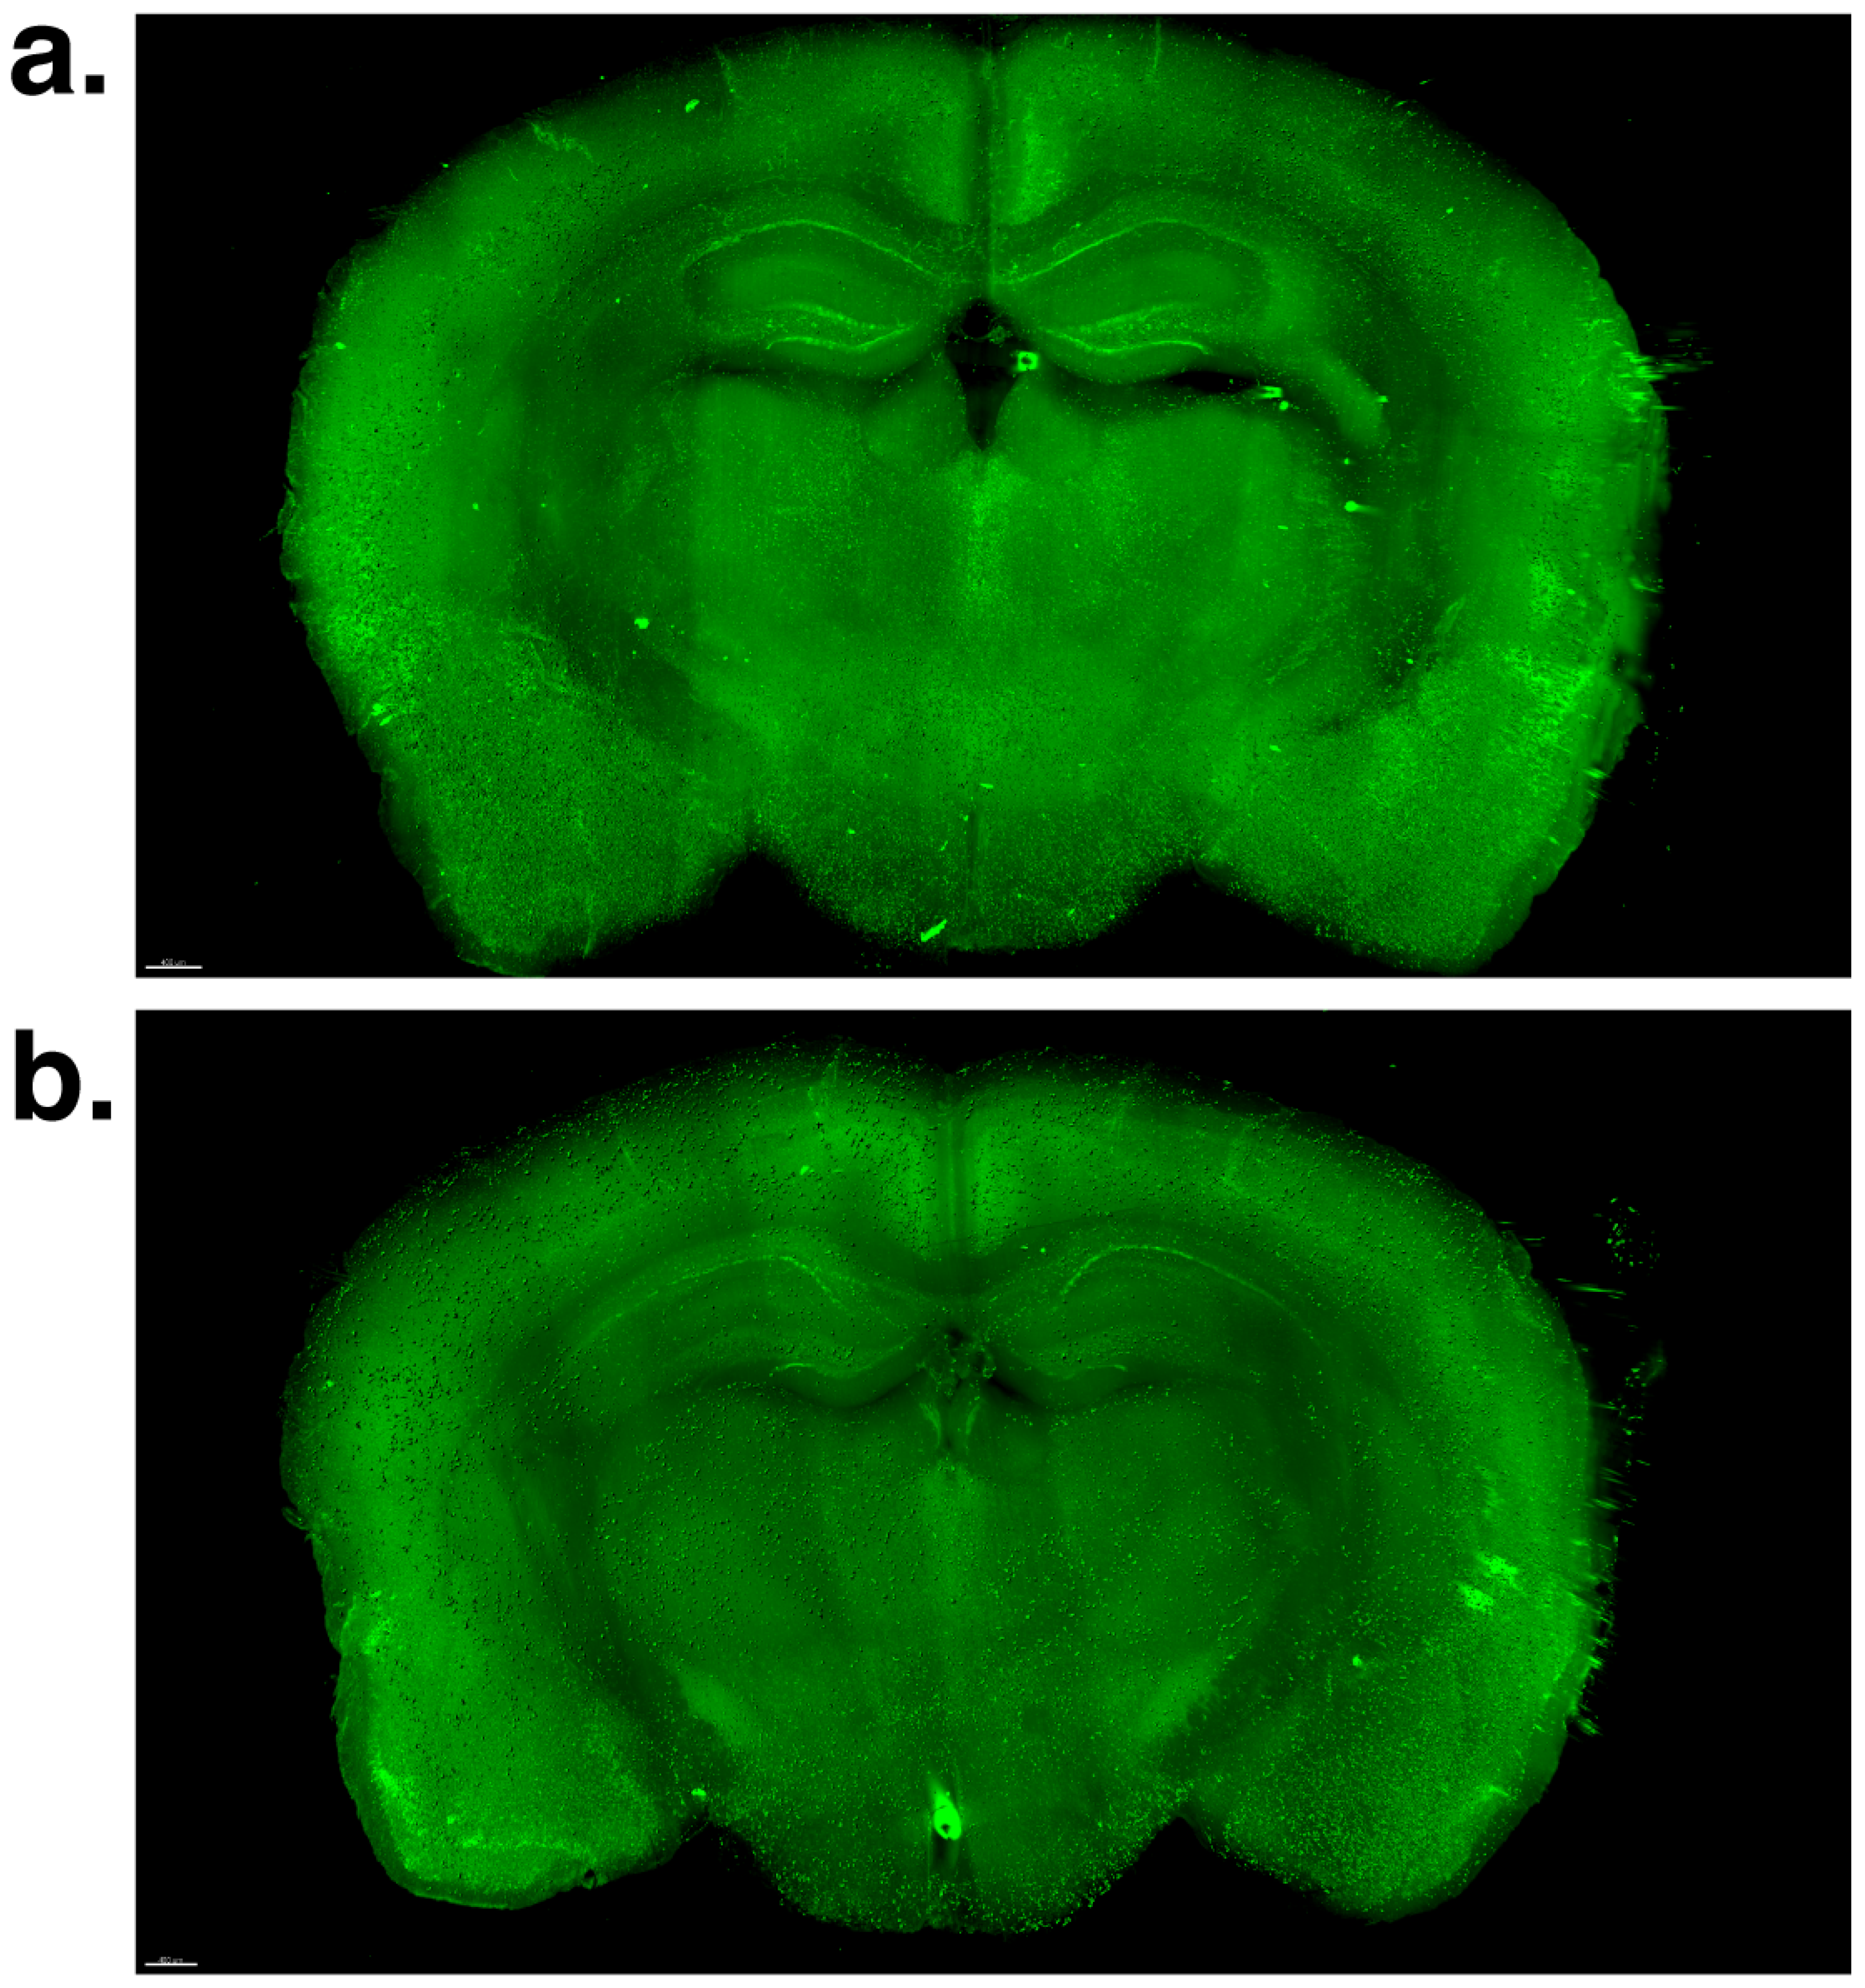

2.2. Effect of Voluntary Swimming on Total β-Amyloid Load and 3D Morphological Features in Brain Macro-LSFM Imaging